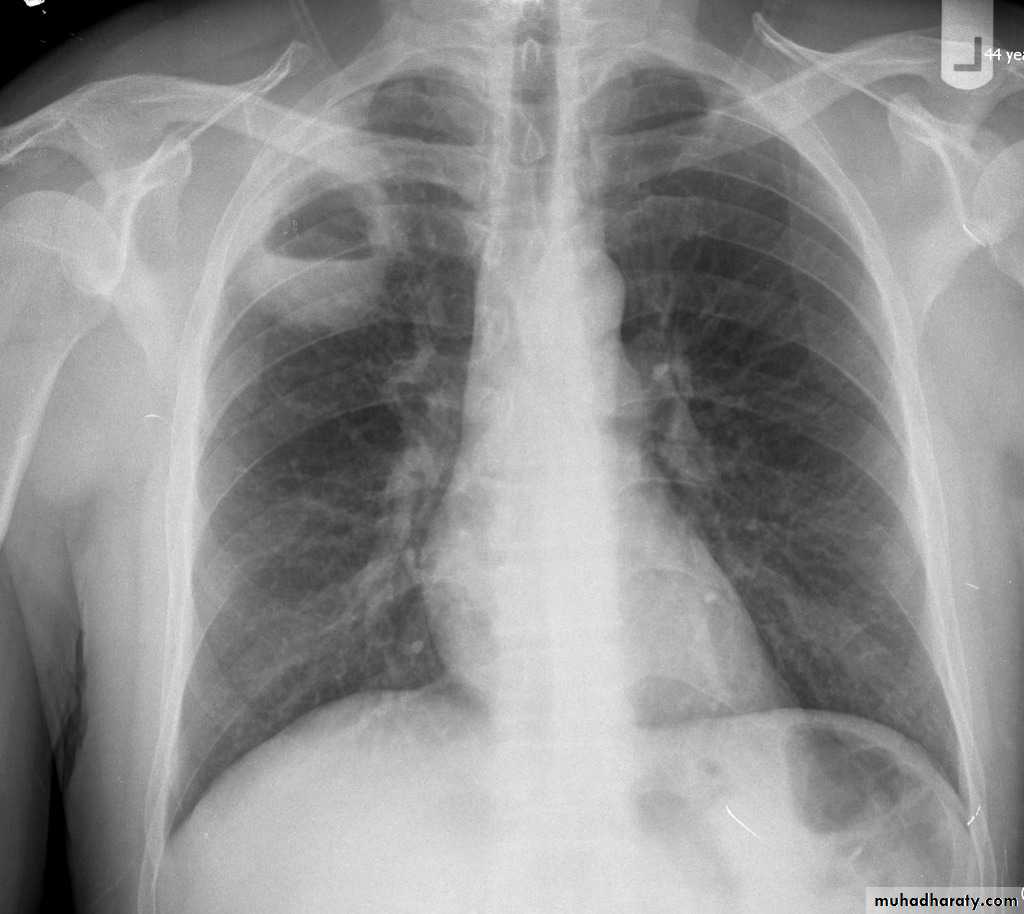

Post primary TB broncho pneumoniacotton wool sign

Post primary TB Bronch pneumonia

60.post primary TB ( cotton wool appearance )

61.post primary TB notice upper apical Broncho pneumonic shadow